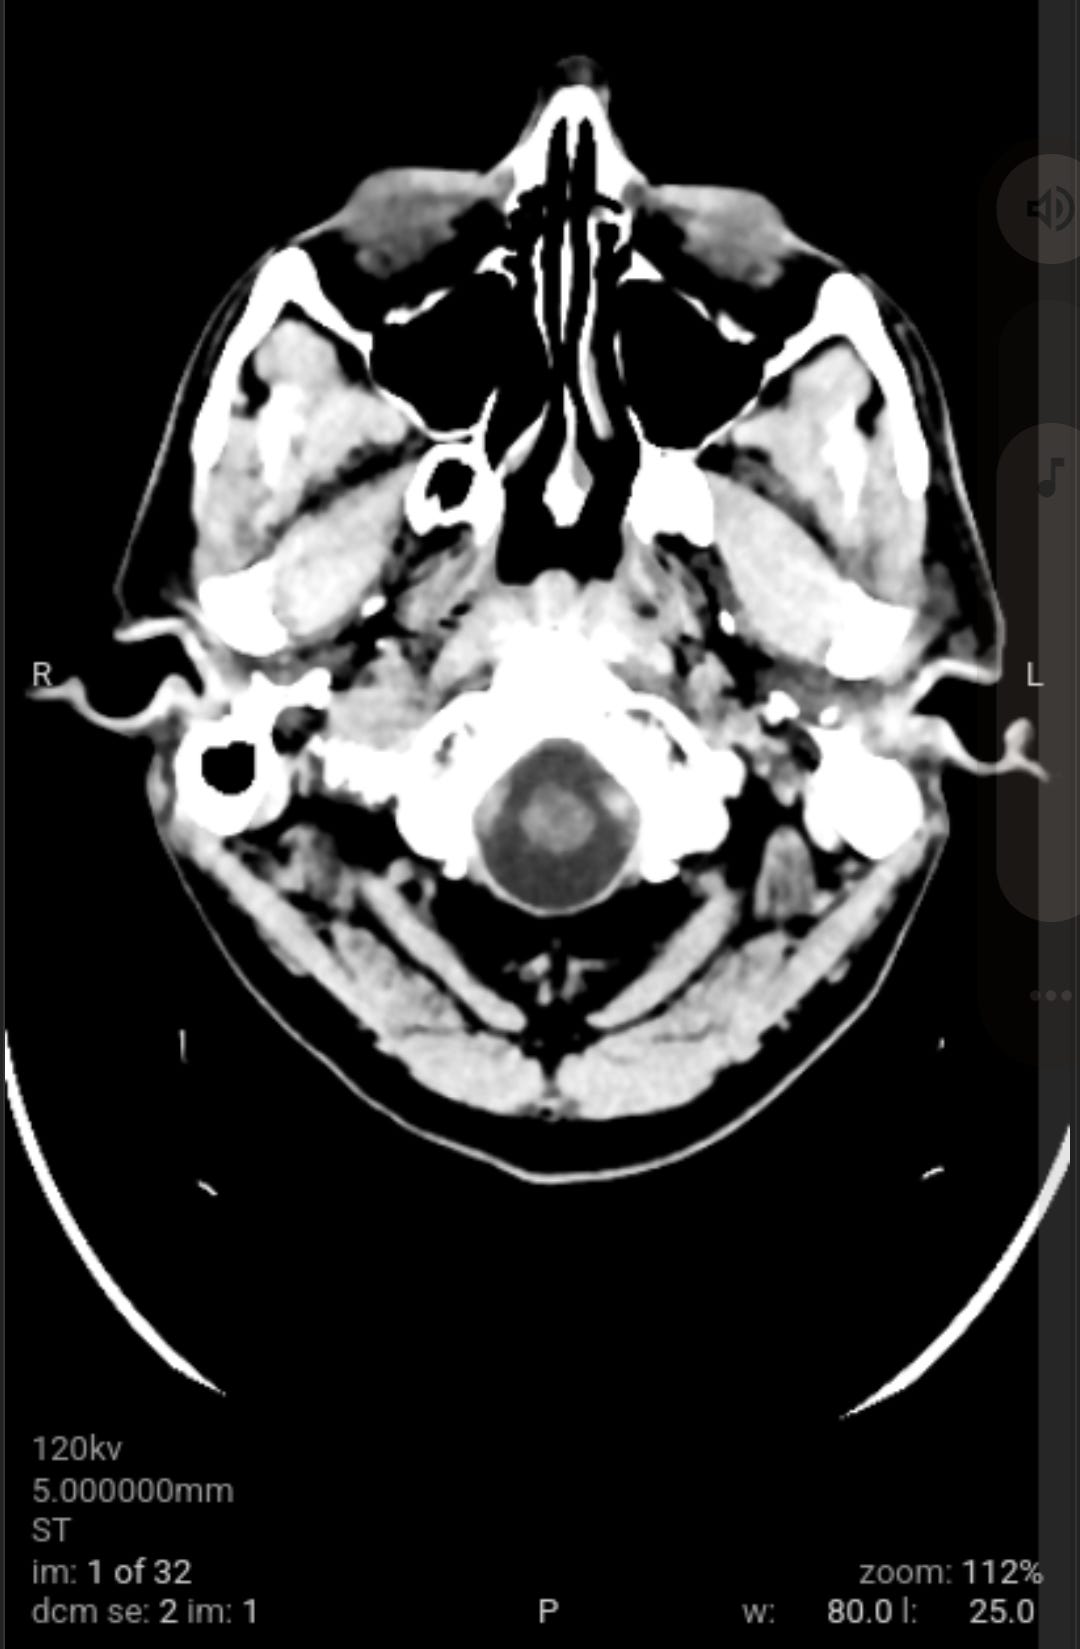

As a followup to eliminate all possible and probably causes of the weaponized audio-video-communications and pathogen nanotechnology. Got blood work and CAT scan done. Results came back good.

As a followup to eliminate all possible and probably causes of the weaponized audio-video-communications CNT and pathogen nanotechnology WPT, I got blood work and CAT scan done yesterday. All came back good with the exception of a low Red Blood Cell RBC count due to my cleansing diet on vegetables and plant based proteins that needs more iron in it with vitamin C, I already dose with vitamin B12 (preference is methylcobalamine). The medical staff could not determine what the unknown material removed from my body was from the salt baths or the material that moved around and itches at times on the left side of my head.

When I had the CAT scan test done, the free electron cascade reaction silenced the CNT local subnet. Anyone who has electronic harassment should know that this is the second time that I have confirmed a free electron cascade reaction destroys the circuitry that is programmed from your prior local environment LOTL CNT and global CNT as well as any mass transfer based CNT subnets. The first time I confirmed CAT scan quenched CNT by free electron cascade reaction was in late 2022 and now again in 2025 (although all of the work done from 2022 through today has significantly reduce the CNT junk, to nearly undetectable levels).

The void spaces on left side are what I suspect to be where the nanotechnology circuitry was removed by magnetic vortex skyrmion unit, chelators, salt water baths, no yeast diet and no added sugar diet. Note the scans do not show any nanotechnology based synthetic biology parasites. This is why the samples pulled from my body were classified as unknown by the western medical staff not trained in the nanotechnology and synthetic biology knowledge domain, a huge gap in Western medicine.